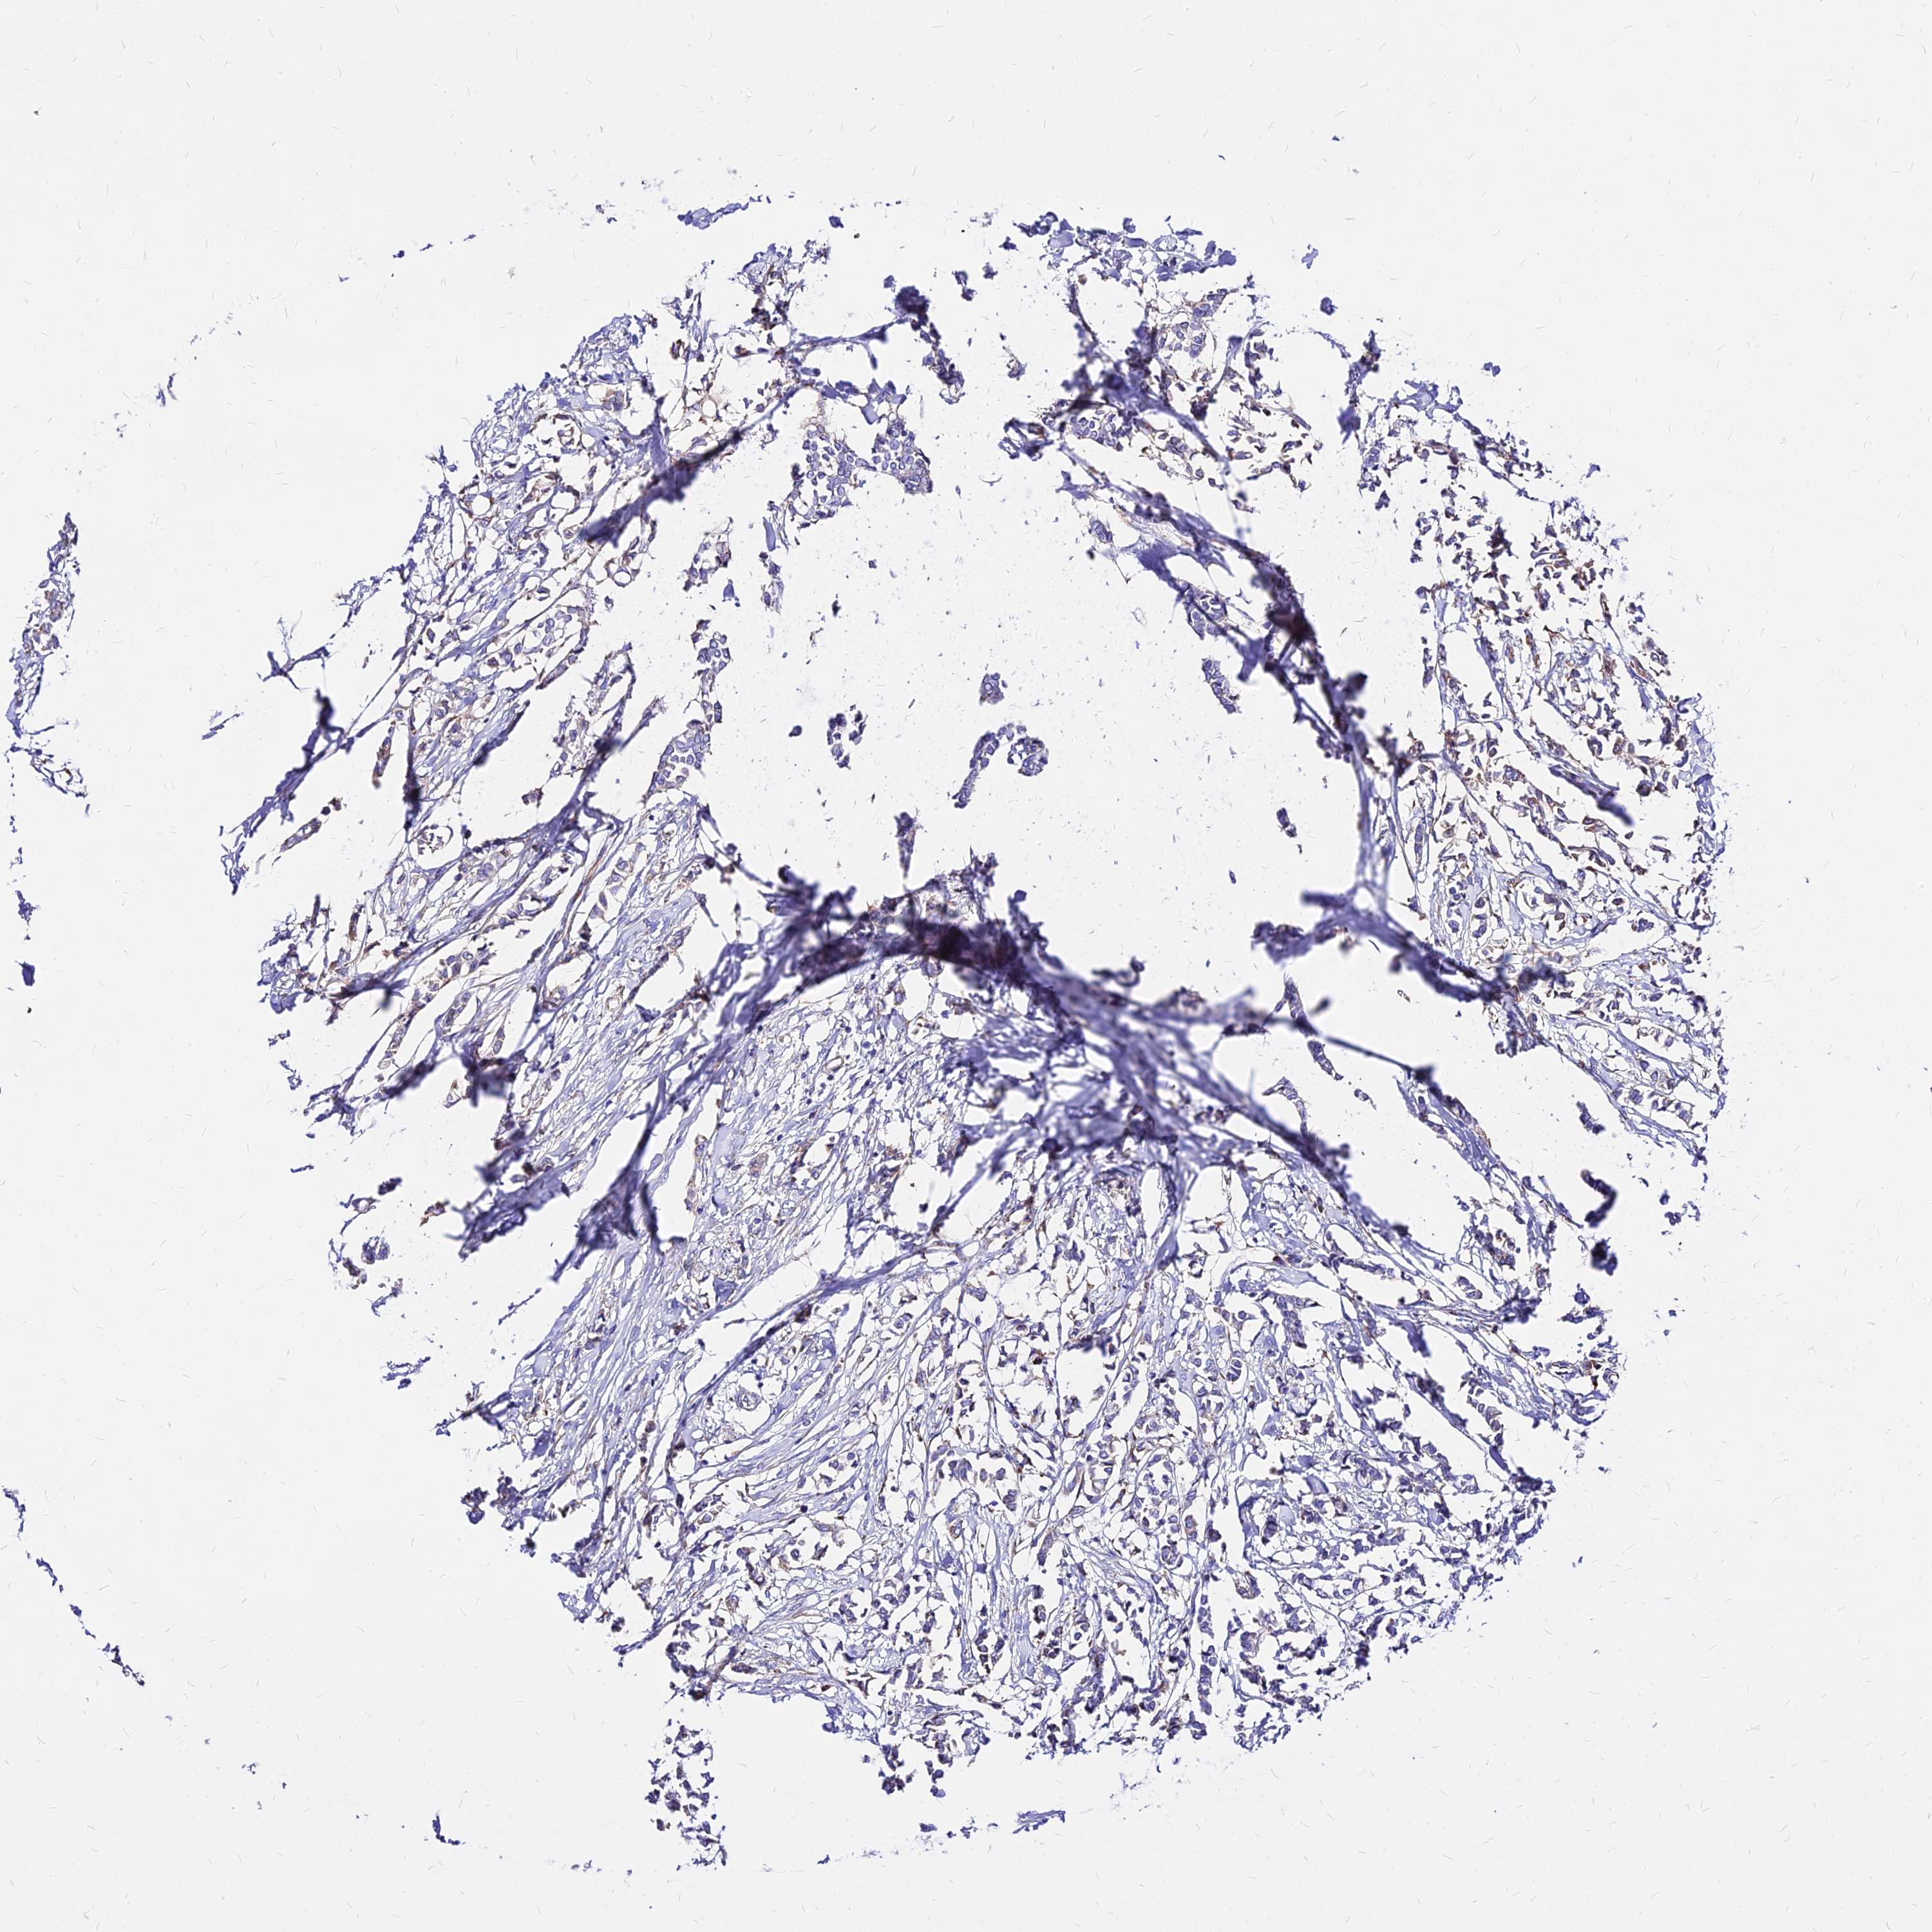

CANCER BREAST CANCER Show tissue menu

BRCA TCGA BRCA VALIDATION PROTEIN EXPRESSION